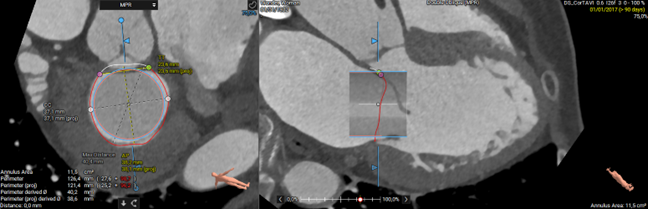

3mensio enables us to screen our patients expeditiously for potential transcatheter mitral valve replacement (TMVR). Determination of the mitral annulus size is a key component of the procedural planning. This can now be achieved across multiple phases with the automatic 3D segmentation of the mitral annulus. Once the appropriate device size is selected, a virtual valve can be placed in the predicted implant position and the neoLVOT can be assessed.

"Preplanning for transcatheter mitral valve replacement (TMVR) is essential because of the risk of LVOT obstruction. Nowadays, the first devices are cleared for clinical use and an increasing number of devices is subject to clinical trials. LVOT and neoLVOT sizes are routinely evaluated for TMVR.

Using the 3mensio Mitral CT workflow, the mitral annulus geometry and LVOT can be easily defined. A virtual valve can be moved through the mitral annular space in all cardiac phases to assess implantation depth and neoLVOT size.